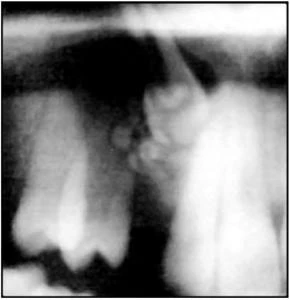

U răng có thể là phức hợp hoặc hỗn hợp và thường được chẩn đoán vô tình trên X quang chỉ khi chúng làm cho răng mọc trễ hoặc răng vĩnh viễn mọc sai vị trí nhiều. Sưng có thể là một phát hiện có liên quan. Sau khi được phát hiện, một u răng nên được loại bỏ ngay khi có thể mà không làm tổn hại những răng kế cận hoặc mầm răng.

Tuỳ thuộc vào vị trí của răng mà sử dụng phương pháp mặt ngoài hay mặt trong để thủ thuật nhổ răng dư. Phim X quang trước phẫu thuật là rất cần thiết để xác định vị trí. Lật vạt như cách thông thường, loại bỏ xương và lấy răng ra với bằng áp lực tối thiểu tránh tổn thương răng cạnh bên. Nếu chân răng cong, tốt nhất là cắt răng và nhổ từng mảnh răng ra.

U răng hỗn hợp có một bao sợi, giúp việc loại bỏ dễ dàng hơn. U răng phức hợp lớn có bề mặt không đều, dính vào xương khiến việc loại bỏ khó khăn. Với trường hợp này cần cắt xương xung quanh cẩn thận.